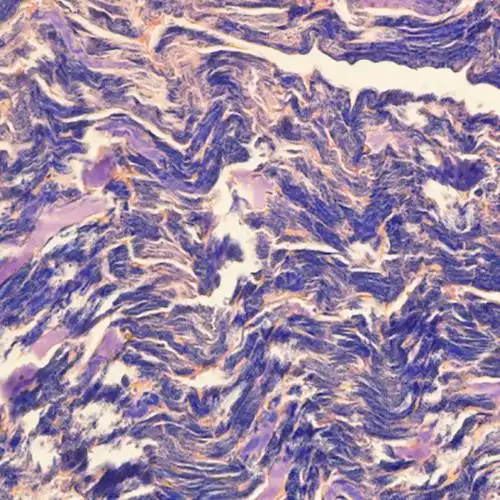

肝,空泡为肝细胞内的脂肪滴图3:酒精性肝炎,箭头所指为mallory小体图4

mallory小体:指肝细胞玻璃样变时,胞质中细胞中间丝前角蛋白变性,多

he×400 mallory小体

枯否细胞增大,有些患者见到特征性mallory小体,类似急性酒精性肝炎,还